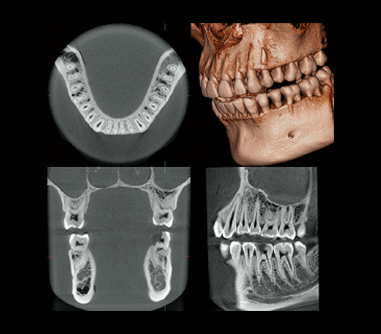

デンタルエックス線写真 SOLIO XZⅡ / SOLIO XZⅡMAXIM | X線撮影装置 | タカラの詳細情報

SOLIO XZⅡ / SOLIO XZⅡMAXIM | X線撮影装置 | タカラ。◇デジタルCMOSセンサー EzSensor Soft サイズ2.0 (25.9×35.9mm。歯科用X線装置選定ガイド - 朝日レントゲン工業株式会社。デンタルエックス線写真斉田 寛之クインテッセンス出版書き込み等もなく比較的綺麗な方かと思います。歯科用X線撮影 - 米沢市立病院。